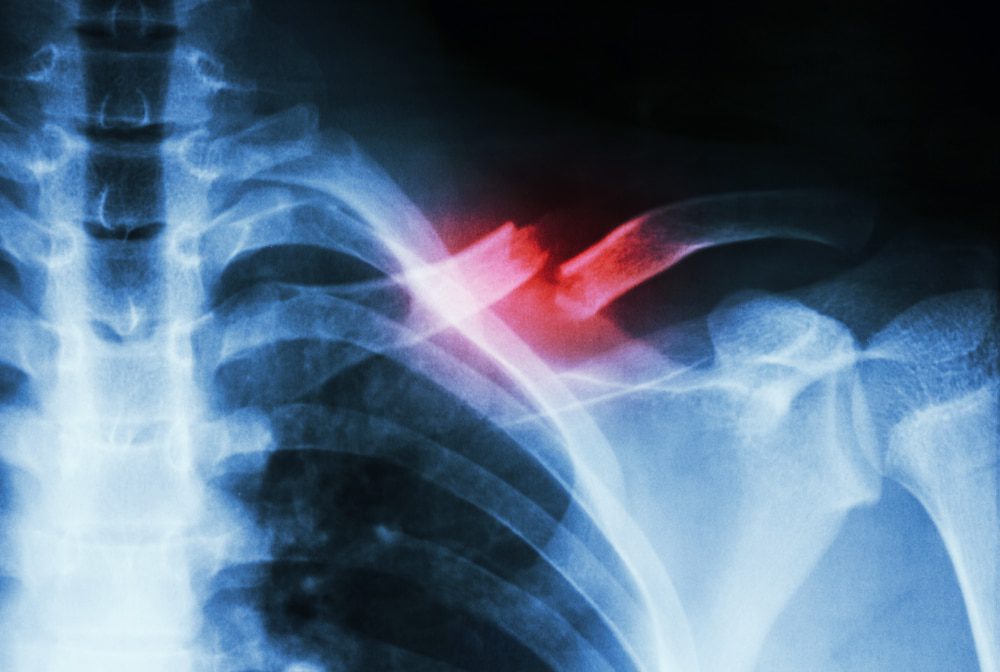

شکستگی استخوان به وضعیتی اطلاق میشود که در آن استخوان به دلایل مختلف از جمله ضربه، فشار یا شرایط بیماریزا مانند پوکی استخوان، شکسته شود. شکستگیها بر اساس نوع آسیب و محل آن به دستههای مختلفی تقسیم میشوند:

شکستگی باز: در این نوع شکستگی، استخوان شکسته از پوست بیرون میزند و میتواند باعث ایجاد عفونت شود.

شکستگی بسته: استخوان شکسته شده اما پوست آسیب ندیده است.

شکستگی عرضی: استخوان به صورت افقی شکسته میشود.

شکستگی طولی: شکستگی به صورت عمودی یا مایل رخ میدهد.

شکستگی چند تکهای: استخوان به چندین تکه تقسیم میشود که معمولاً نیاز به جراحی دارد.

شکستگیهای فشاری: این نوع شکستگی بهویژه در استخوانهای ضعیفتر، مثل ستون فقرات، رخ میدهد.

عکسبرداری با اشعه ایکس: یکی از رایجترین و دقیقترین روشها برای تشخیص شکستگی است.